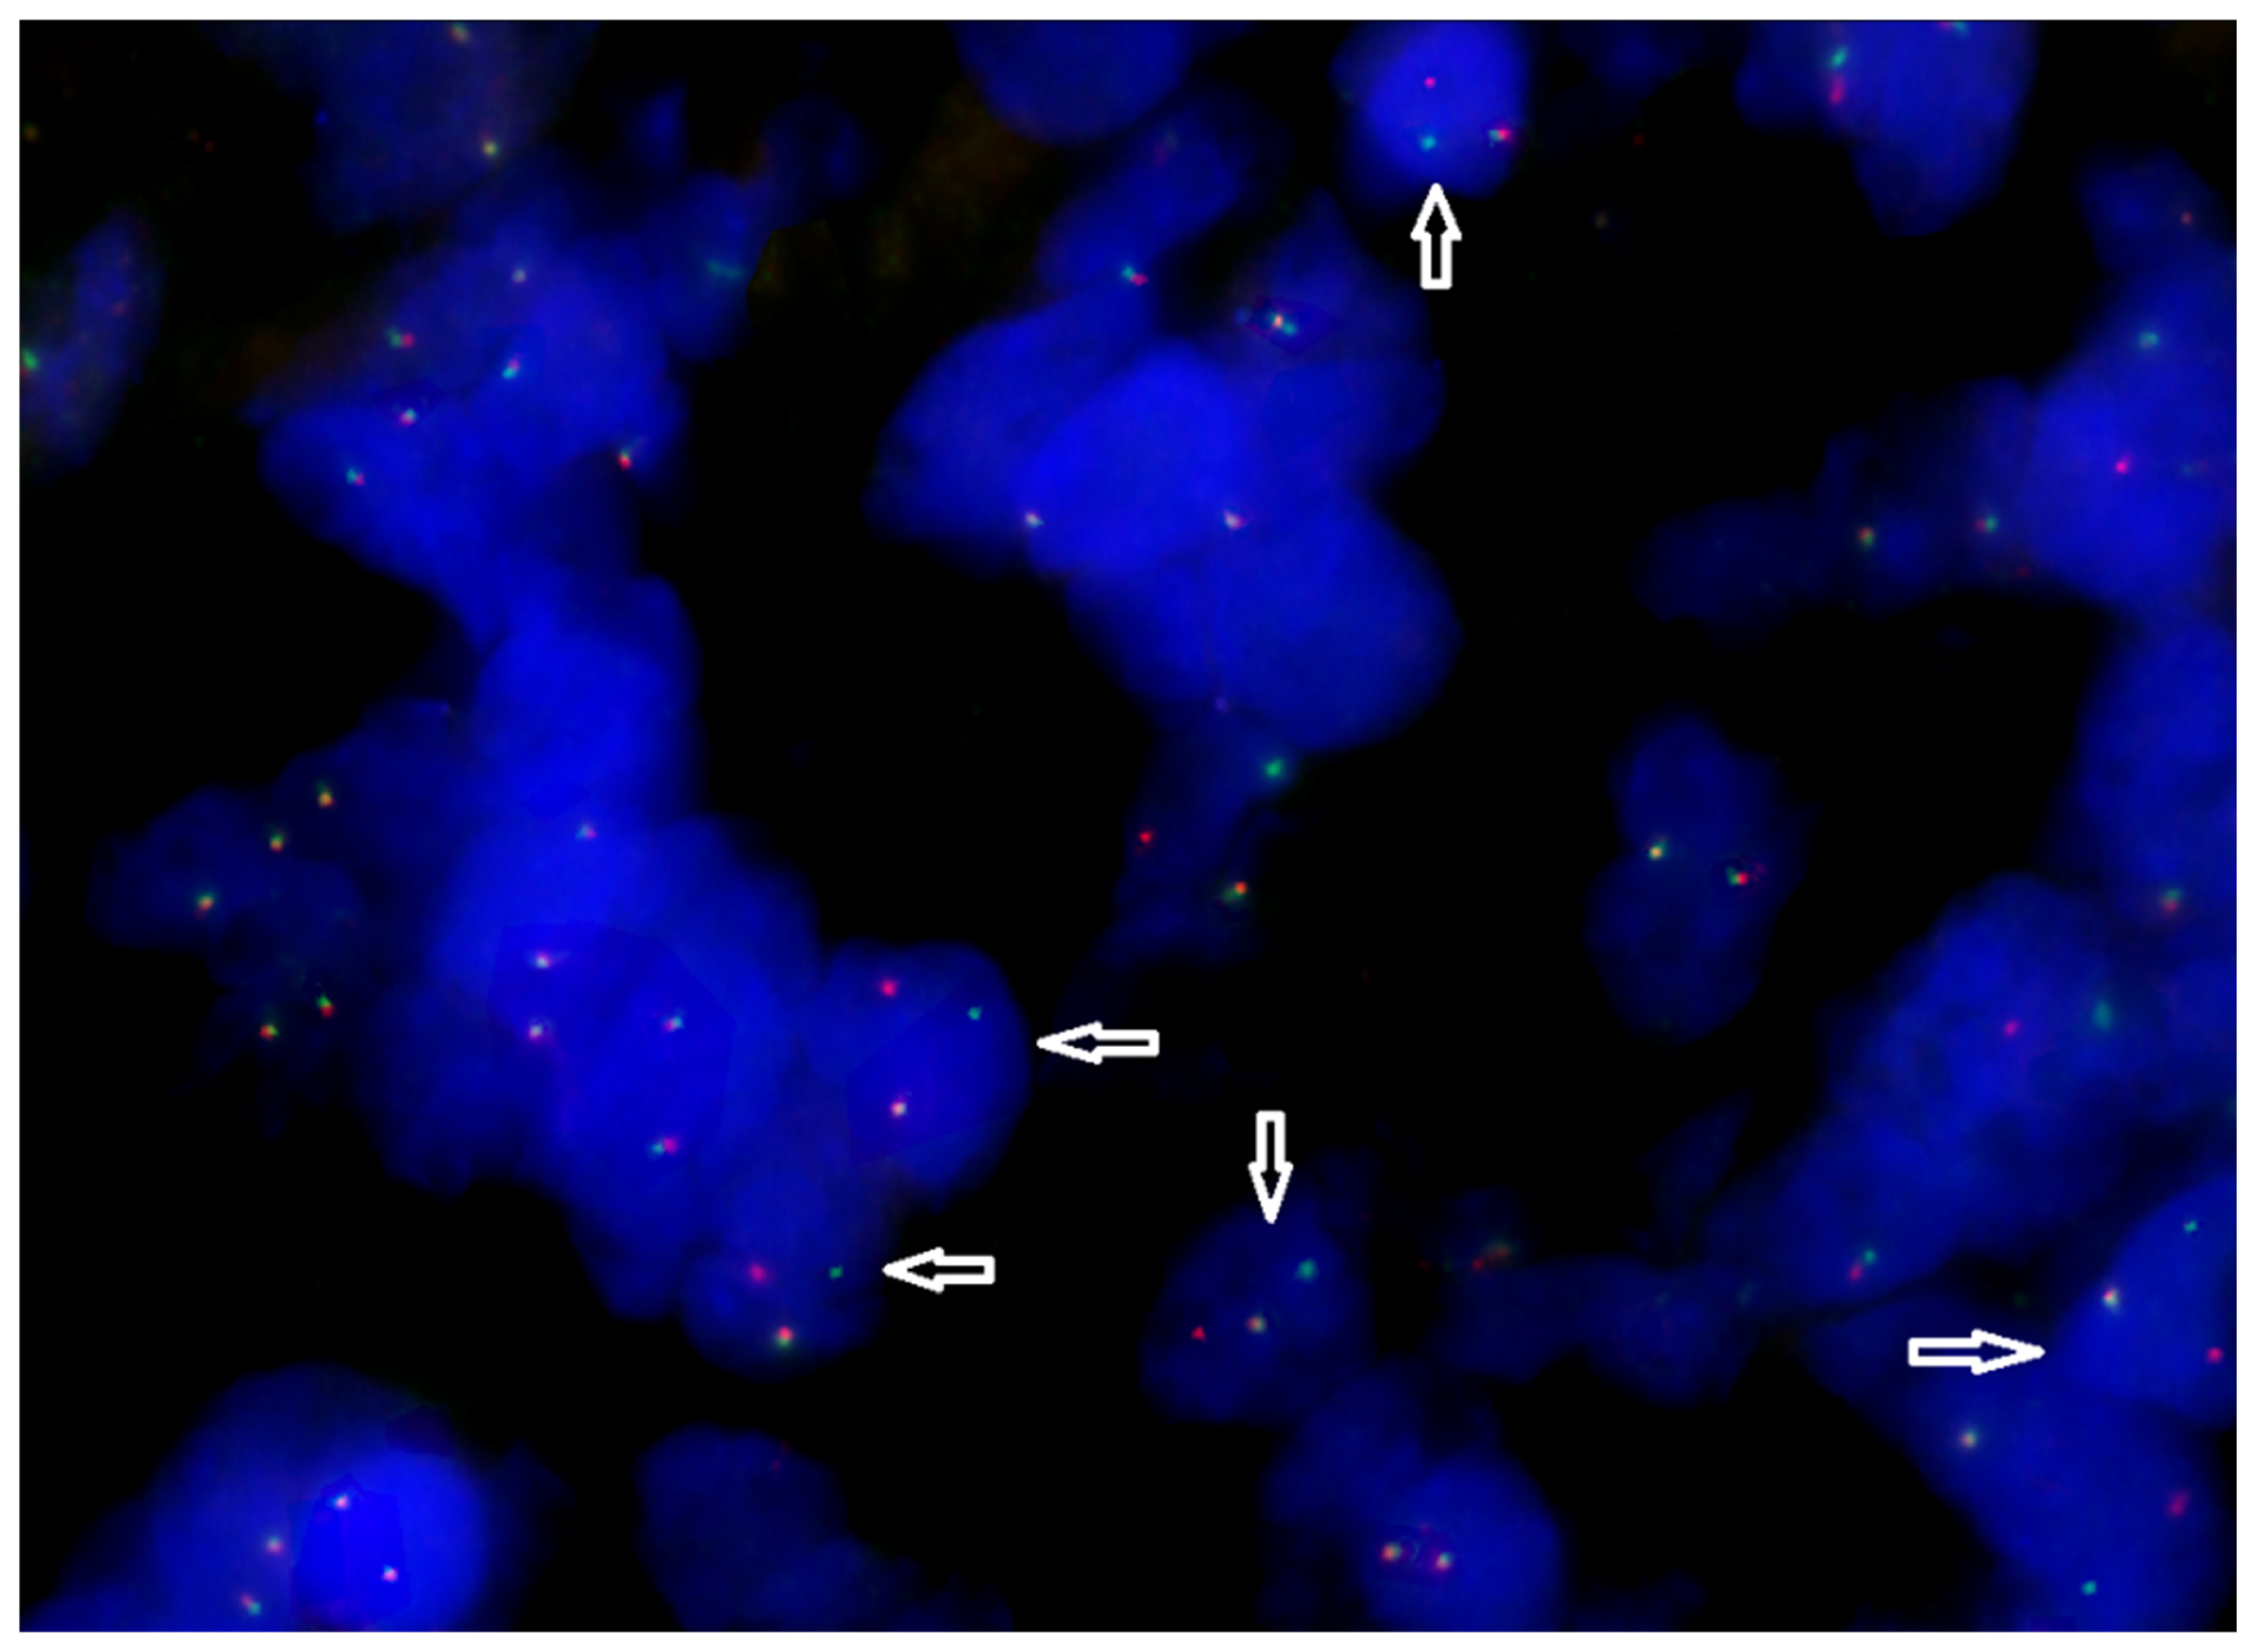

2.2. Retrospective Assessment of the Tumor Molecular Profile